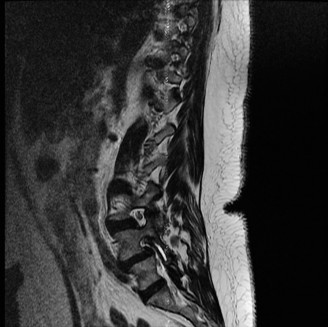

Magnetic Resonance Imaging and the Posterior Ligamentous Complex

To definitively assess the integrity of the soft tissue stabilizers and the neural elements, a Magnetic Resonance Imaging (MRI) scan without contrast was performed. Historically, textbooks propagated the "50-50-25 rule," suggesting that a burst fracture was inherently unstable if it exhibited >50% canal compromise, >50% loss of vertebral body height, or >25 degrees of kyphosis. Modern spine trauma surgery has largely debunked this rigid radiographic dogma. We now understand that these bony metrics alone do not dictate mechanical instability. The true arbiter of stability is the Posterior Ligamentous Complex (PLC).

The MRI, particularly the Short Tau Inversion Recovery (STIR) and T2-weighted sagittal sequences, provided the definitive diagnosis. The images demonstrated profound hyperintensity and discontinuity of the ligamentum flavum, the interspinous ligaments, and the supraspinous ligaments at the T12-L1 level. The facet joint capsules were also disrupted, indicated by fluid within the joints. This complete failure of the PLC means the posterior tension band is gone. Regardless of the bony parameters, this spine cannot resist physiological flexion loads. If treated non-operatively, this injury will inevitably lead to progressive kyphosis, delayed neurological deficit, and intractable pain.